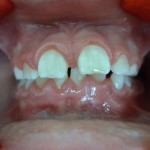

Photos avant et après traitement par Bielle

vue de face